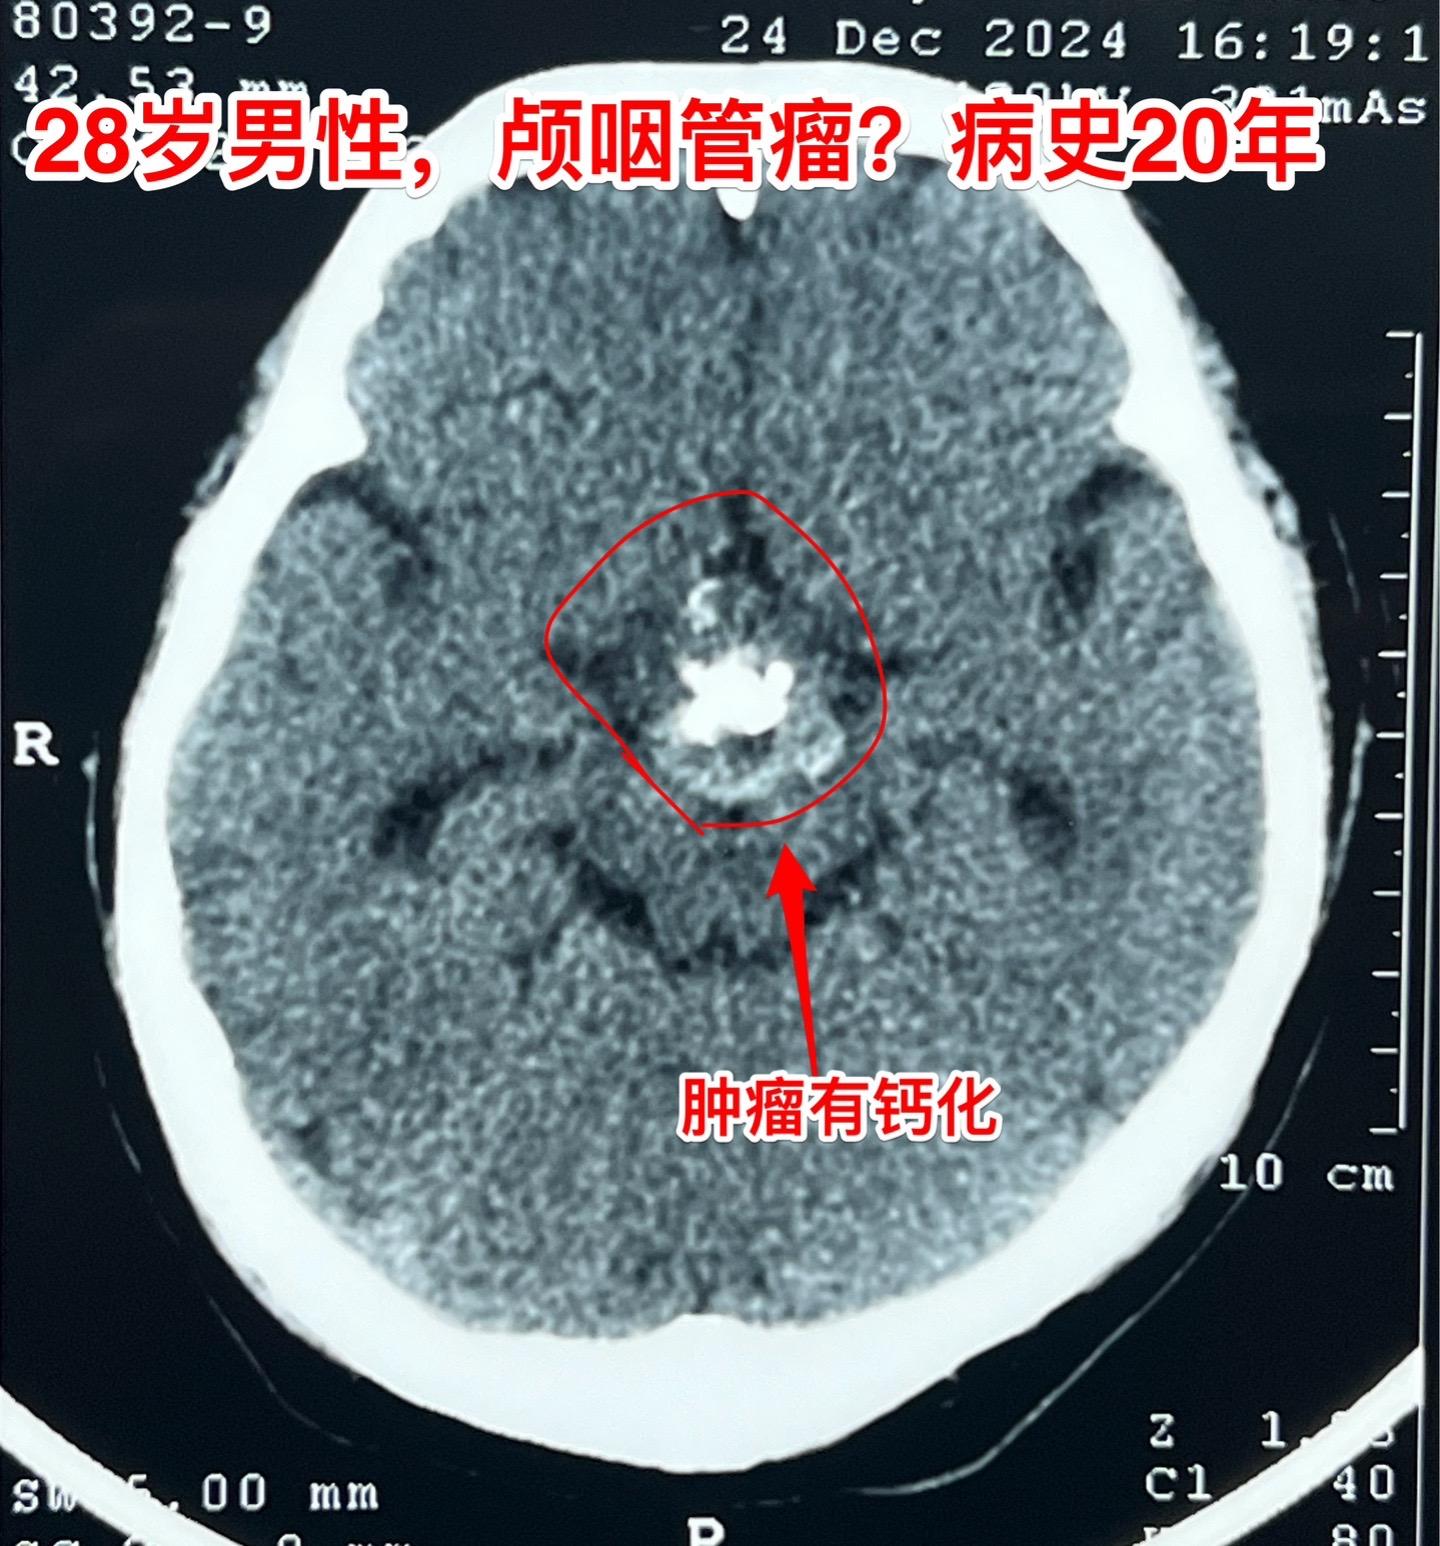

鞍区肿瘤长了20年,才下决心作手术!元旦之后的第一个鞍区肿瘤手术,怀疑是颅咽管瘤。 患者为28岁男性,20年前就发现脑部长了肿瘤,当时患者才八岁,三博脑科医院刚刚成立不久,他们就到三博脑科医院就医。因故未作手术,密切观察。 患者随后能正常读书,生长发育也还不错。后来还考上了大学,毕业后曾经在上海工作过。多次复查磁共振显示鞍区肿瘤体积在增大。而且患者也感觉视力方面出现了问题,在多个著名的医院就医过,最后下决心来找我作手术。 一月三日手术中发现肿瘤中心有钙